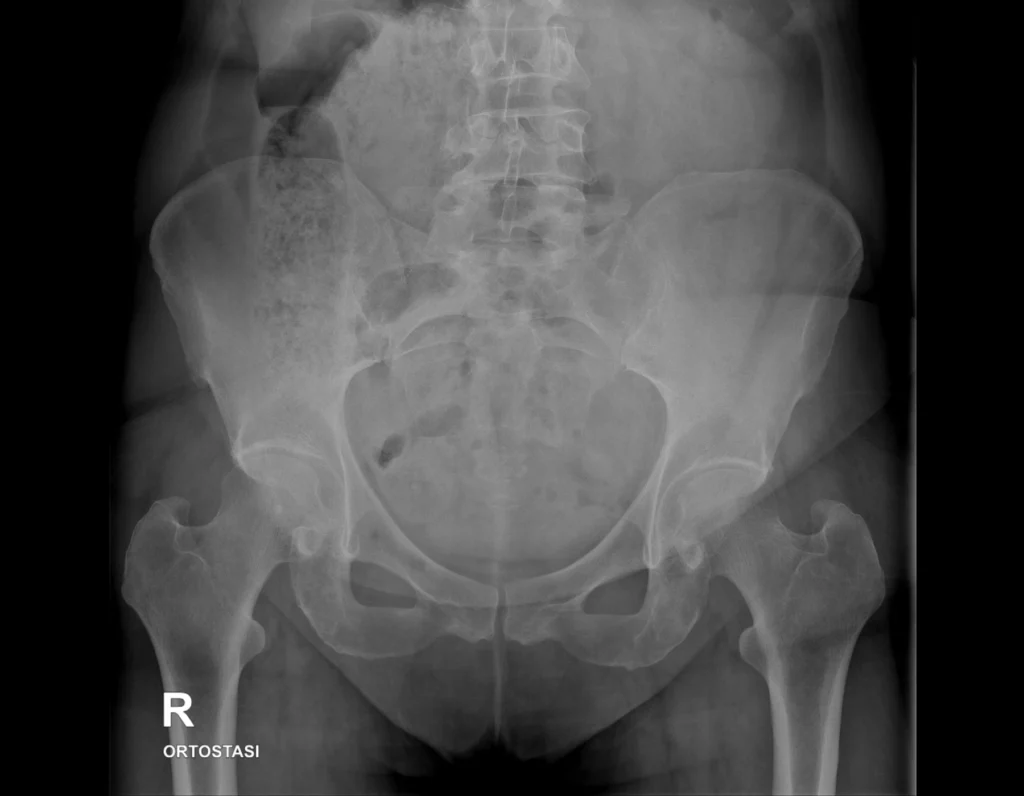

Radiografía simple de abdomen utilizada como ejemplo docente para identificar la densidad grasa y su rol como contraste natural.

Se identifican áreas de densidad intermedia, ligeramente más radiolúcidas que las partes blandas, correspondientes al tejido adiposo, que delimita y separa las estructuras abdominales.

La grasa presenta una atenuación mayor que el aire y menor que las partes blandas, por lo que se visualiza como un gris oscuro en la radiografía.

Su presencia permite delimitar órganos y planos anatómicos, actuando como un contraste natural.

- La grasa es más radiolúcida que las partes blandas.

- Se visualiza como un gris oscuro.

- Facilita la identificación de estructuras abdominales.